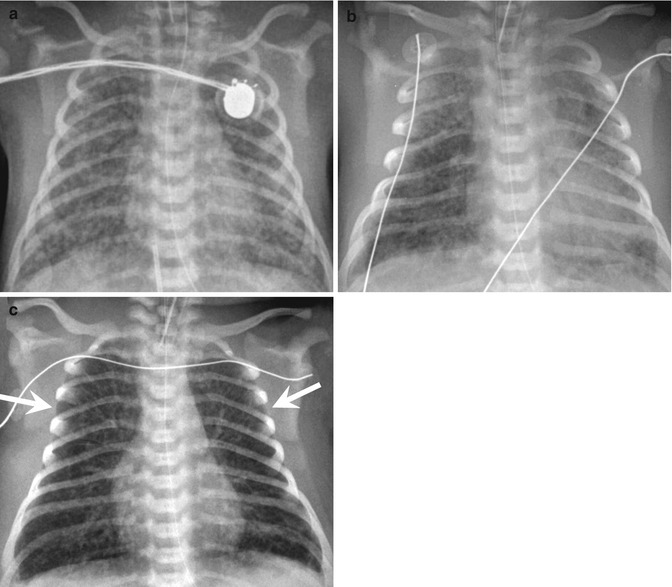

Apnoea can present on the first day of life and is virtually universal in preterm infants born at <28 weeks gestational age (Fig. 47.8) (Henderson-Smart 1981). The severity of apnoea is defined by its duration, the degrees of associated oxygen desaturation and bradycardia, and the type of therapeutic intervention provided, from minimal stimulation to total respiratory support. The assessment of the apnoeic patient consists of the nose-to-diaphragm then the head-to-toe approach. Apnoea of prematurity is differentiated from periodic breathing, a repetitive series of pauses in breathing separated by a crescendo-decrescendo pattern of breaths. Periodic breathing in normal preterm infants is considered benign, but it can be associated with hypocarbia, hypoxia and CNS hypoxia/ischaemia and with a fall in sub-glottic airway volume (Khan et al. 2005; Rigatto 1986). Conditions resulting in apnoea, including structural lesions (Brazy et al. 1987), are considered before a diagnosis of idiopathic apnoea is made (Fig. 47.9). Upper airway contact with food or with gastric contents can result in apnoea, but episodes of gastroesophageal reflux do not appear to be temporally linked to apnoea. In animals, prior upper airway exposure to acid can alter the response to subsequent mechanical loads (Sant’Ambrogio et al. 1998). Thus, the clinical impression that the two are related may be indirect. Pre-existing anaemia exacerbates the apnoeic response to SLN stimulation in animals and is important in postoperative apnoea (Cote et al. 1995). However, blood transfusion therapy for apnoea of prematurity is debated.

Fig. 47.8.

Incidence of apnoea of prematurity. The incidence of apnoea of prematurity increases inversely with the gestational age at birth, being virtually universal in the preterm infant <28 weeks (Modified and reproduced with permission from Henderson-Smart (1981))